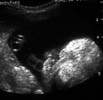

En cas d’atteinte bilatérale, le bourgeon médian peut réaliser une masse centrale saillante à ne pas confondre avec un tératome ou un probocis. Il est limité par des encoches anéchogènes et semble appendu au nez.